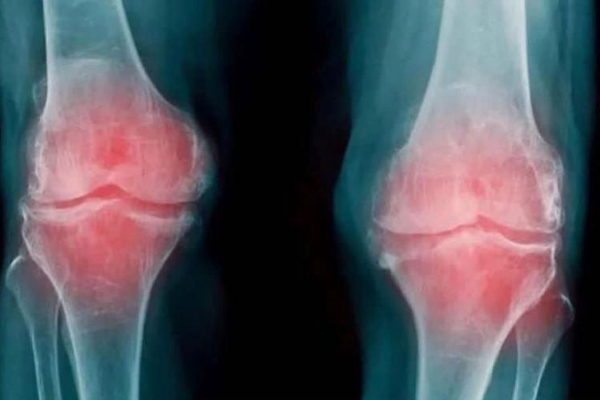

¿Te duele la rodilla? Cuidado, podría ser artrosis y aquí te contamos cuáles son...

La artrosis de rodilla, por lo general, se desarrolla lentamente y la progresión del dolor suele seguir la misma progresión, aunque puede cursar con...